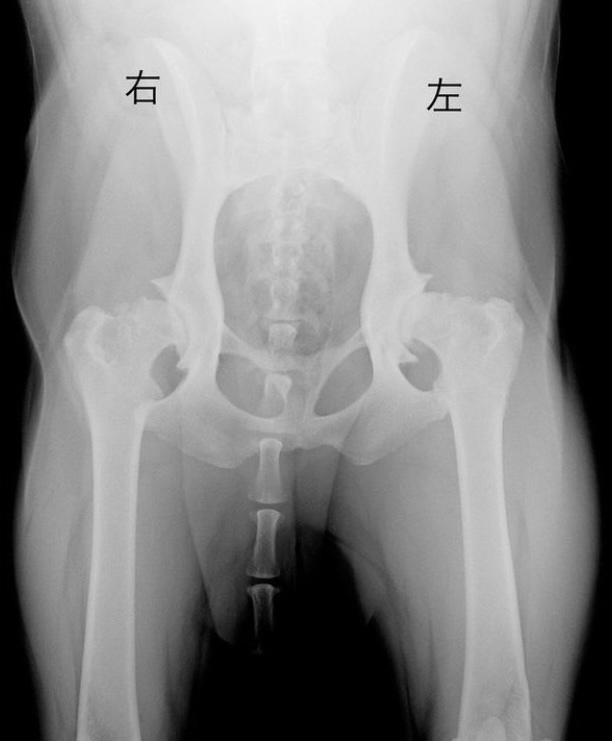

左膝の靭帯を損傷した場合、高い確率で反対の膝の靭帯を損傷する可能性があるとのこと。即日、検査の為、急遽1泊の入院検査。CT、レントゲン、血液検査を実施しました。次の日の検査結果で、右膝の前十字靭帯断裂と股関節・膝の関節炎の進行が判明。股関節形成不全の手術をする前に、まずは膝の手術(TPLO)が必要との結果でした。

右脚と左脚のレントゲンを比較すると、筋肉量が落ちてしまい右脚が細くなっていました。1泊の入院検査で8万円かかりました。右膝の手術で60万円程度。股関節形成不全の手術(人工股関節全置換手術)が片足だけで130万円程度。股関節形成不全の手術を行っても合併症を併発した場合、さらに手術が必要になり費用も発生する可能性があります。

股関節形成不全とは、大腿骨骨頭が骨盤にきれいにはまっておらず、おさまりが浅かったりすることで、このままの状態では、将来的に歩行が困難になること、最悪の場合は股関節の脱臼が考えられるそうです。また、後ろ脚に問題があり、跛行やかばう動作が続くと必ず前足の肘部分を痛めてしまうそうです。 股関節形成不全の原因のほとんどが遺伝だと言われました。

『右後脚の膝前十字靭帯断裂』と『股関節の関節炎進行』が判明。担当獣医より、股関節の手術をする前に、右膝の手術が必要との診断を受けました。